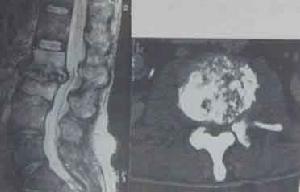

本病大部分可出現急性腹痛,神經根性痛,髖關節痛,或嚴重敗血症等症狀。在一些病例中,炎性細胞浸潤椎旁軟組織可形成椎旁膿腫,表現為受累椎體、椎間盤及相鄰椎體的椎旁軟組織增厚,橫斷面病變呈環繞椎體的軟組織腫塊影,膿腫範圍累及硬膜外間隙可致使硬膜囊腹側受壓呈弧形改變,嚴重時累及脊髓,甚至脊髓嚴重受壓變形,引起截癱。

(3)、MRI表現為椎體呈長T1、長T2異常信號,FLAIR序列及增強掃描對明確診斷有很大幫助;

椎體及附屬檔案破壞變形,呈長T1、長T2信號改變,椎體邊緣信號異常部分與正常分界模糊,椎間盤失去正常形態及信號,呈不同程度的腫脹增厚或破壞、碎裂,椎間隙有不同程度狹窄,呈長T1、更長T2改變,椎前、椎旁軟組織腫脹,T1WI上與肌肉組織相似,T2WI上信號更高,邊緣有線樣低信號影可能為膿腫壁,增強掃描後,受累椎體、間盤及寒性膿瘍的周邊有異常對比增強。臨床有結核病史及結核中毒症狀。